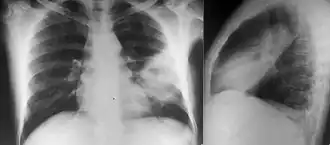

Diabetes mellitus is one of the most important risk factors in developing melioidosis. The disease should be considered in anyone who has spent time in endemic areas who develops a fever, pneumonia, or abscesses in their liver, spleen, prostate, or parotid gland.[1] The clinical manifestation of the disease can range from simple skin changes such as abscesses or ulcerations to severe organ problems.[7] The commonest organs affected are liver, spleen, lungs, prostate, and kidneys. Among the most common features are bacteremia (in 40 to 60% of cases), pneumonia (50%), and septic shock (20%).[1][8] People with only pneumonia may have a prominent cough with sputum and shortness of breath. However, those with septic shock together with pneumonia may have minimal coughing.[3] Results of a chest X-ray can range from diffuse nodular infiltrates in those with septic shock to progressive consolidation located most commonly in the upper lobes for those with pneumonia only. Pleural effusion and empyema are more common for melioidosis affecting lower lobes of the lungs.[3] In 10% of cases, people develop secondary pneumonia caused by other bacteria after the primary infection.[2] In northern Australia, 60% of the infected children presented with only skin lesions, while 20% presented with pneumonia.[2]

Various imaging modalities can also help with the diagnosis of melioidosis. In acute melioidosis with the spreading of the bacteria through the bloodstream, the chest X-ray shows multifocal nodular lesions. It may also show merging nodules or cavitations. For those with acute melioidosis without the spread to the bloodstream, chest x-ray most commonly shows upper lobe consolidation or cavitations.[9] In chronic melioidosis, the slowly progressing of upper lobe consolidation of the lungs resembles tuberculosis.[9] For abscesses located in other parts of the body apart from the lungs, especially in the liver and spleen, CT scan has higher sensitivity when compared with an ultrasound scan. In liver and splenic abscesses, an ultrasound scan shows "target-like" lesions while CT scan shows "honeycomb sign" (abscess with loculations separated by thin septa) in liver abscesses.[9] For melioidosis involving the brain, MRI have higher sensitivity than a CT scan in diagnosing the lesion. MRI shows ring-enhancing lesions for brain melioidosis.[9]